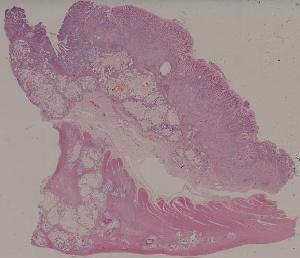

60.胃溃疡

61.胃腺癌(胃粘液腺癌)

62.急性普通型病毒性肝炎

63.慢性活动性肝炎

64.急性重型病毒性肝炎

65.亚急性重型病毒性肝炎

66.活动性结节性肝硬化

67.非活动性结节性肝硬化

68.胆汁性肝硬化

69.肝细胞性肝癌

72.膜性肾小球肾炎

73.急性肾小球肾炎

74.新月体性肾炎

75.慢性硬化性肾小球肾炎